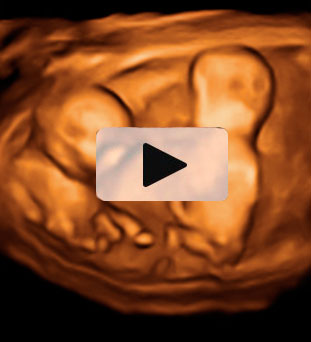

Ecografía 3D de la semana 11: Feto de perfil

Se distinguen partes de su cara

En la ecografía en 3D de este feto de 11 semanas de embarazo se pueden distinguir sus extremidades superiores e inferiores ya formadas, así como el esbozo de las orejas y una incipiente nariz.

Ecografía 3D de feto de 11 semanas, de perfil

Este bebé tiene tan sólo 11 semanas de gestación, pero ya podemos identificar muchos de sus órganos y estructuras básicas (huesos del brazo y la pierna, fontanela, ojo, nariz y oreja...). Puede apreciarse el cordón umbilical y la pared uterina sobre la que se apoya.